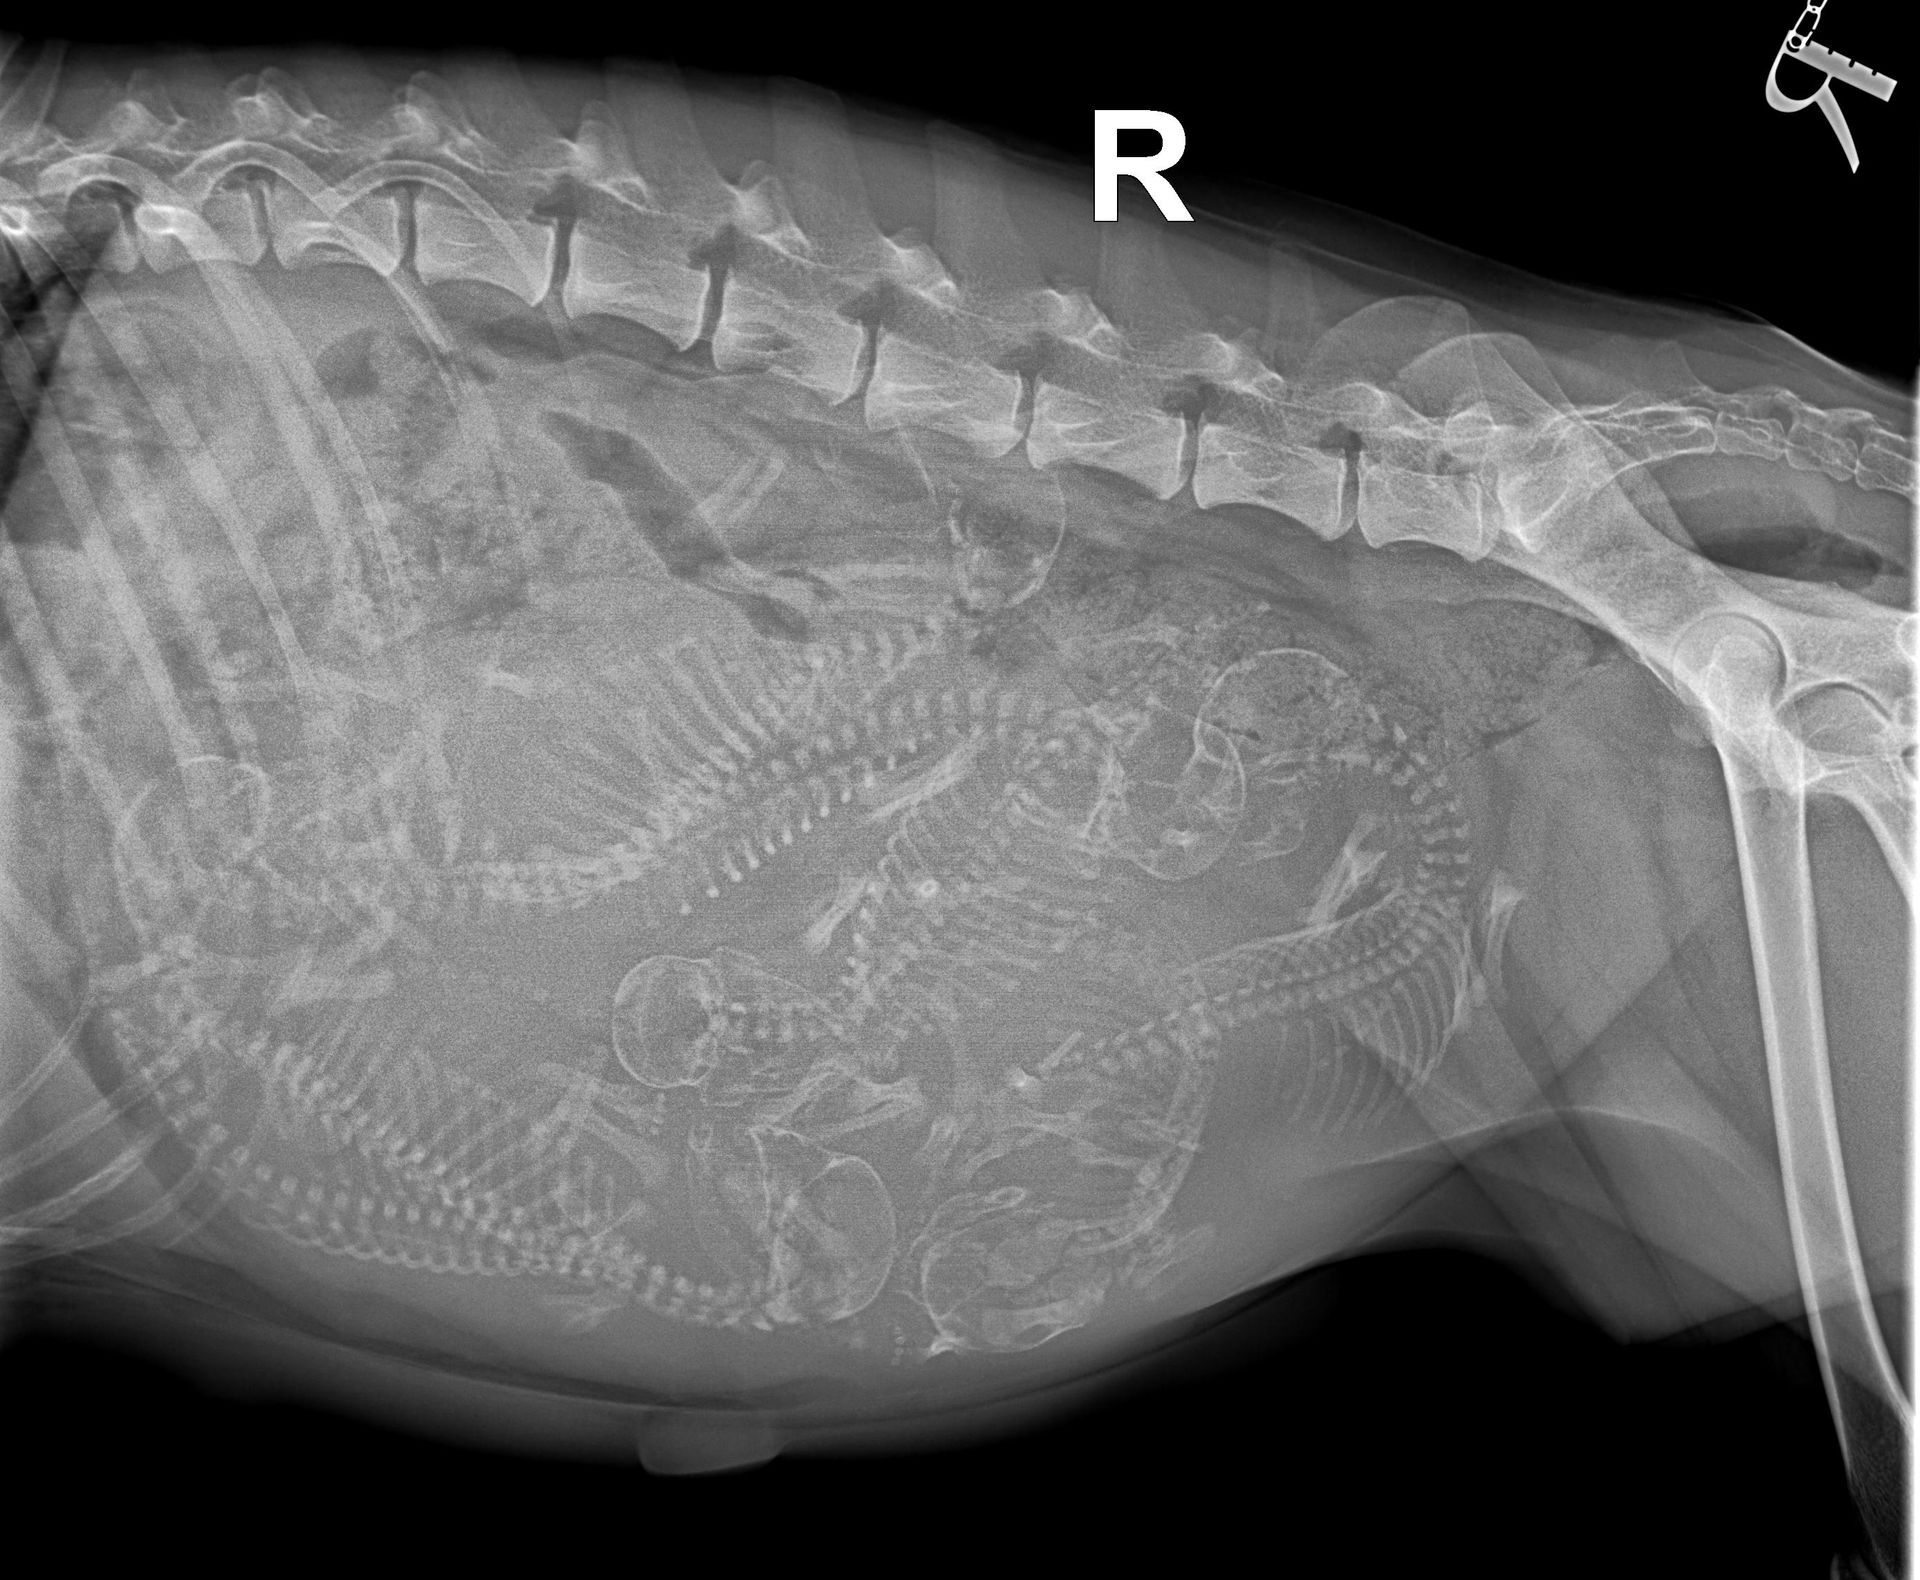

Unsere Kleien Maus bekommt sieben Welpen, noch sehen sie aus wie kleine Seepferdchen aber bald werden kleine Welpen geboren.